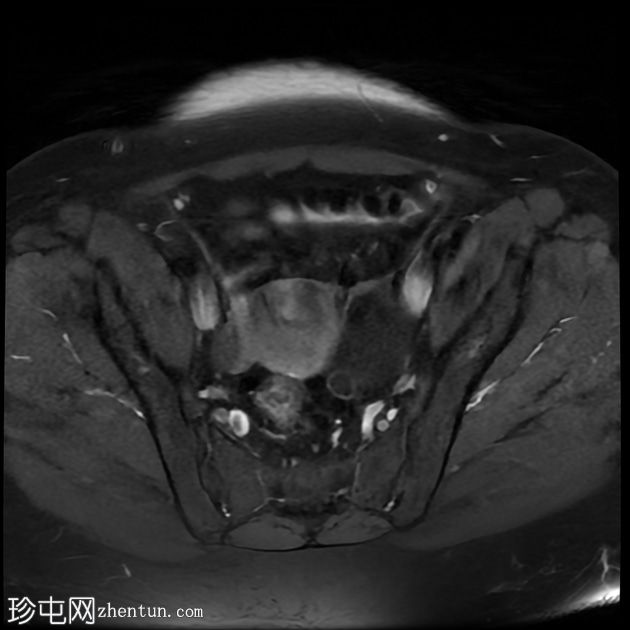

轴位

T2加权像

左侧卵巢增大,呈弥漫性低T1信号和高T2信号,可见周边卵泡,部分卵泡除周边卵泡周围有环状强化外,无明显实质强化。左侧附件蒂呈漩涡状,提示卵巢扭转。